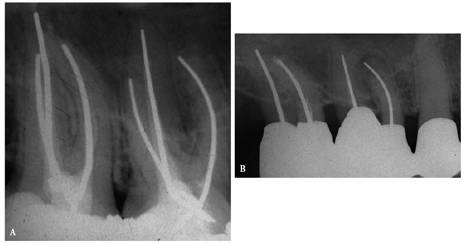

angulations of the suspected tooth (Figures 19-24A

and B).

Comparing varied views is essential in diagnosing the presence of additional

roots, anatomic configurations, anomalies, and other unusual circumstances that

may complicate the treatment.

Figure 19-24A and B: (A) Pretreatment radiograph of a mandibular premolar shows one canal. (B) A second radiograph taken from an angulation of 15 degrees from the mesial discloses a second root.